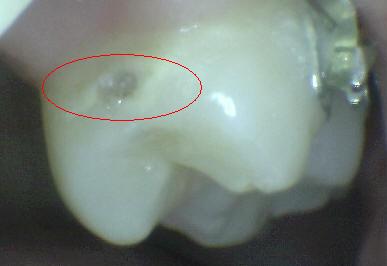

Código 4

(Caries Moderada): Sombra oscura

de dentina subyacente al esmalte intacto con o sin interrupción

localizada del esmalte

-

Esta lesión aparece como una sombra de decoloración

visible a través de una superficie de esmalte intacta, la que puede o no mostrar signos

de descomposición localizada del esmalte, como la microcavidad y /o discontinuida

< 0,5mm. después del secado con aire durante 5

segundos

La aparición de

la sombra se ve a menudo con más facilidad cuando

el diente está húmedo. El área oscura es una

sombra intrínseca que puede aparecer gris, negro-azul o

marrón-anaranjado,

a través de las paredes del esmalte vestibular, lingual o

palatino